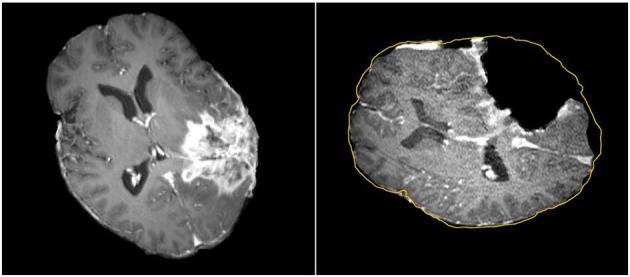

In image-guided neurosurgery, co-registered preoperative anatomical, functional, and diffusion tensor imaging can be used to facilitate a safe resection of brain tumors in eloquent areas of the brain. However, the brain deforms during surgery, particularly in the presence of tumor resection. Non-Rigid Registration (NRR) of the preoperative image data can be used to create a registered image that captures the deformation in the intraoperative image while maintaining the quality of the preoperative image. Using clinical data, this paper reports the results of a comparison of the accuracy and performance among several non-rigid registration methods for handling brain deformation. A new adaptive method that automatically removes mesh elements in the area of the resected tumor, thereby handling deformation in the presence of resection is presented. To improve the user experience, we also present a new way of using mixed reality with ultrasound, MRI, and CT. This study focuses on 30 glioma surgeries performed at two different hospitals, many of which involved the resection of significant tumor volumes. An Adaptive Physics-Based Non-Rigid Registration method (A-PBNRR) registers preoperative and intraoperative MRI for each patient. The results are compared with three other readily available registration methods: a rigid registration implemented in 3D Slicer v4.4.0; a B-Spline non-rigid registration implemented in 3D Slicer v4.4.0; and PBNRR implemented in ITKv4.7.0, upon which A-PBNRR was based. Three measures were employed to facilitate a comprehensive evaluation of the registration accuracy: (i) visual assessment, (ii) a Hausdorff Distance-based metric, and (iii) a landmark-based approach using anatomical points identified by a neurosurgeon. The A-PBNRR using multi-tissue mesh adaptation improved the accuracy of deformable registration by more than five times compared to rigid and traditional physics based non-rigid registration, and four times compared to B-Spline interpolation methods which are part of ITK and 3D Slicer. Performance analysis showed that A-PBNRR could be applied, on average, in <2 min, achieving desirable speed for use in a clinical setting. The A-PBNRR method performed significantly better than other readily available registration methods at modeling deformation in the presence of resection. Both the registration accuracy and performance proved sufficient to be of clinical value in the operating room. A-PBNRR, coupled with the mixed reality system, presents a powerful and affordable solution compared to current neuronavigation systems.

在图像引导的神经外科手术中,术前共配准的解剖、功能和扩散张量成像可用于促进在脑功能区安全切除脑肿瘤。然而,手术过程中大脑会发生变形,尤其是在进行肿瘤切除时。术前图像数据的非刚性配准(NRR)可用于创建一个配准图像,该图像能捕捉术中图像的变形,同时保持术前图像的质量。本文利用临床数据报告了几种处理脑变形的非刚性配准方法在准确性和性能方面的比较结果。提出了一种新的自适应方法,该方法能自动去除切除肿瘤区域的网格元素,从而处理存在切除情况时的变形。为了改善用户体验,我们还提出了一种将混合现实与超声、MRI和CT结合使用的新方法。本研究聚焦于在两家不同医院进行的30例胶质瘤手术,其中许多手术涉及切除较大体积的肿瘤。一种基于自适应物理的非刚性配准方法(A-PBNRR)为每位患者配准术前和术中MRI。将结果与其他三种现成的配准方法进行比较:在3D Slicer v4.4.0中实现的刚性配准;在3D Slicer v4.4.0中实现的B样条非刚性配准;以及在ITKv4.7.0中实现的PBNRR(A-PBNRR基于此)。采用了三种措施来全面评估配准准确性:(i)视觉评估;(ii)基于豪斯多夫距离的度量;(iii)使用神经外科医生确定的解剖点的基于地标方法。与刚性和传统基于物理的非刚性配准相比,使用多组织网格自适应的A-PBNRR将可变形配准的准确性提高了五倍多,与作为ITK和3D Slicer一部分的B样条插值方法相比提高了四倍。性能分析表明,A-PBNRR平均可在不到2分钟内应用,达到了临床环境中使用所需的速度。在模拟存在切除情况时的变形方面,A-PBNRR方法的表现明显优于其他现成的配准方法。配准的准确性和性能都证明足以在手术室中具有临床价值。与当前的神经导航系统相比,A-PBNRR与混合现实系统相结合提供了一种强大且经济实惠的解决方案。